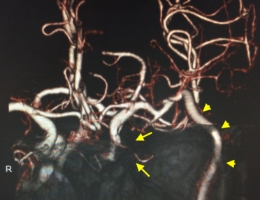

治療前

物が二重に見えるようになって発症した内頚動脈大型動脈瘤(矢印)の症例です。クリッピング術で直接動脈瘤をつぶすことができないため、バイパス術(矢印)を増設し内頚動脈を遮断することで動脈瘤を治療しました。